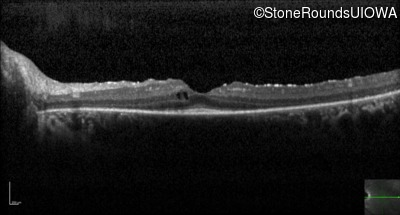

Optical Coherence Tomography - Left -

20/20 -2

Exemplar / OCT Stack